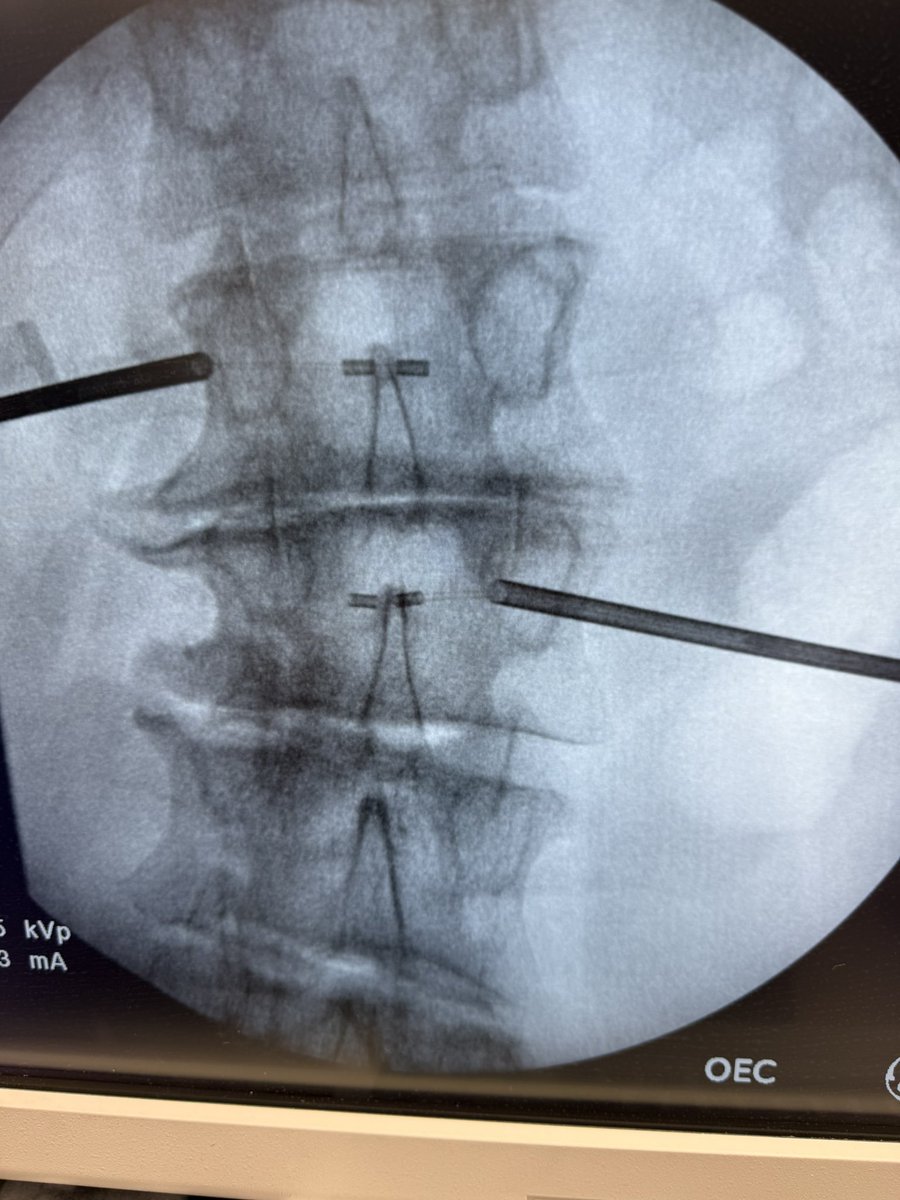

Had a chance to use the Stryker BVN ablation system. Seven minute ablation at 95° C. Easy to use and the case went flawlessly.